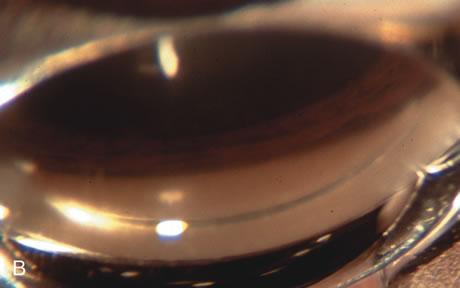

Nonpenetrating procedures as they exist today generally decrease postoperative complications but do not reduce IOP as successfully as trabeculectomy.140 The success rate also appears to be highly dependent on race, length of topical antiglaucoma therapy, and prior ocular surgery.141,142 Deep sclerectomy combined with phacoemulsification results in an IOP reduction similar to phacotrabeculectomy at one year with comparable visual outcome.143 Phacoviscocanalostomy lowers IOP by approximately 33%144 through either a one- or two-site approach145 (Fig. 4). Nonpenetrating procedures are in evolution, and their place in long-term glaucoma care is still unclear.

Fig. 4. Viscocanalostomy with deep sclerectomy and phacoemulsification. Nonpenetrating filtration procedures (NPFS) may be combined with phacoemulsification. Patients with mild disc damage and a history of limited topical drug therapy are the best candidates. Patients who require an IOP in the low teens are not good candidates for NPFS. By definition, NPFS is designed to lower IOP without penetrating into the anterior chamber, thereby avoiding the complications associated with trabeculectomy. Viscocanalostomy is intended to allow aqueous to percolate through a trabeculodescemetic membrane into a subscleral cavern created by the deep sclerectomy. The aqueous diffuses from the cavern into the dilated ostia of Schlemm's canal and into the episcleral venous plexus. A. Fashion a uniform 300-micron superficial scleral flap 1 mm into clear cornea. B. Construct a second 600-micron deep flap that facilitates the unroofing of Schlemm's canal, seen as the darker area. C. Use viscoelastic to dilate the ostia of Schlemm's canal. The major problem with viscocanalostomy is the eventual closure of the ostium decreasing flow to the episcleral plexus. D. Dissect the deep flap anteriorly into clear cornea creating the trabeculodescemetic membrane. This membrane is clearly seen between the scleral spur and the bend of the deep flap. The integrity of this membrane ensures the nonpenetrating portion of the surgery. Another problem with NPFS is the eventual fibrosis of this initially transparent membrane requiring goniopuncture. E. Deep sclerectomy gets its name from removal of the deep flap. Removal of this flap creates the potential subscleral space for accumulation of aqueous before it enters Schlemm's canal and exits the episcleral venous plexus. After removal of the deep flap, the superficial flap is sutured into place and conjunctiva closed. Approximately half of these procedures develop a shallow bleb.